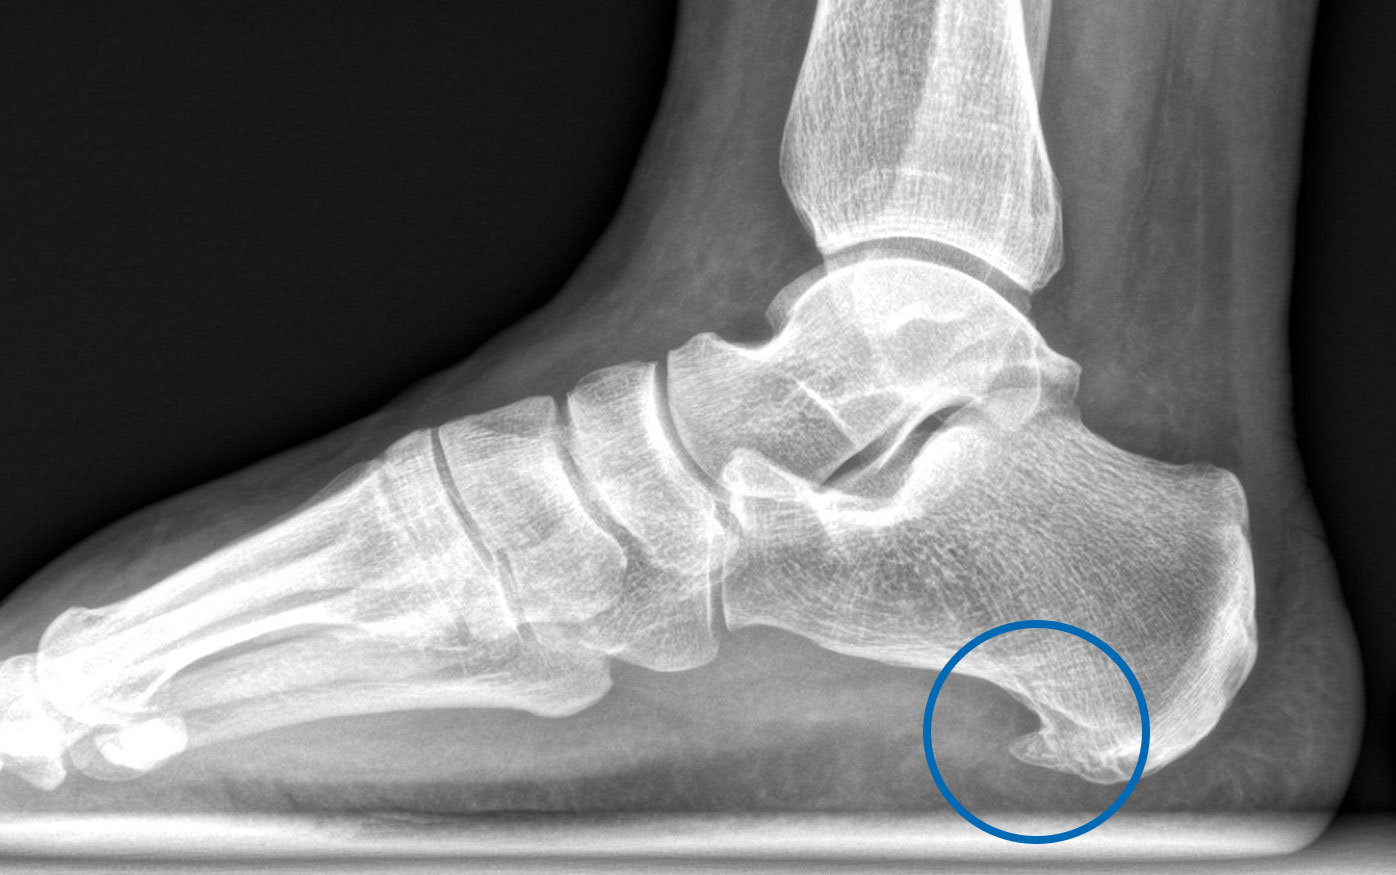

Fersensporn und Plantarfasziitis

Der Fersensporn oder auch Kalkaneussporn ist eine knöcherne Ausziehung (Knochenneubildung) am Fersenbein, die sehr gut im seitlichen Röntgenbild zu sehen ist. Dieser Sporn führt nicht zwangsläufig zu Schmerzen. Häufig kommt er aber zusammen mit einer Entzündung der Plantarfaszie vor, der sogenannten Plantarfasziitis, die Beschwerden verursacht.

Bild: Universitätsklinik Balgrist

Liegen die typischen Symptommerkmale vor, lässt sich die Diagnose der Plantarfasziitis in der klinischen Untersuchung bereits stellen. Ohne weitere Abklärungen kann eine gezielte konservative Therapie eingeleitet werden *. Eine standardmässige Röntgenuntersuchung zur Diagnosesicherung ist nicht notwendig und dient lediglich zum Ausschluss relevanter Differenzialdiagnosen bei entsprechendem Verdacht – z. B. bei Unfällen *,*. Bei Bedarf kann eine Magnetresonanztomographie (MRT bzw. engl. MRI für magnetic resonance imaging) die Diagnose weiter sichern *.